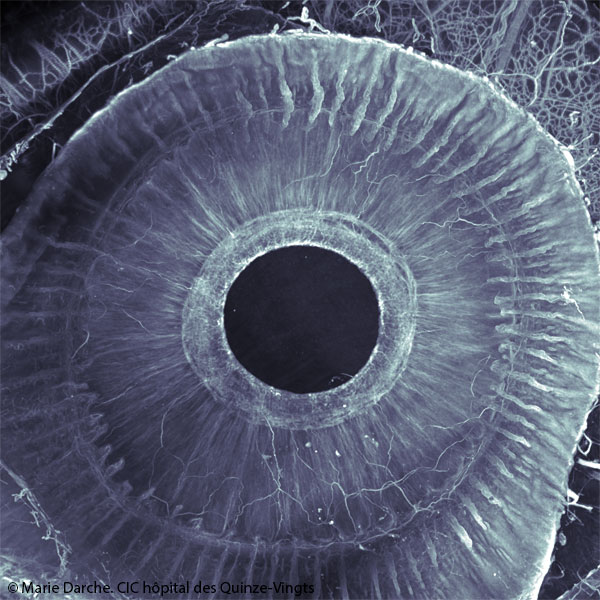

Segment antérieur de l’œil observé grâce à une méthode de transparisation puis un double marquage. En bleu le collagène 4, présent dans les parois des vaisseaux sanguins. En violet, la tubuline, qui indique les nerfs.